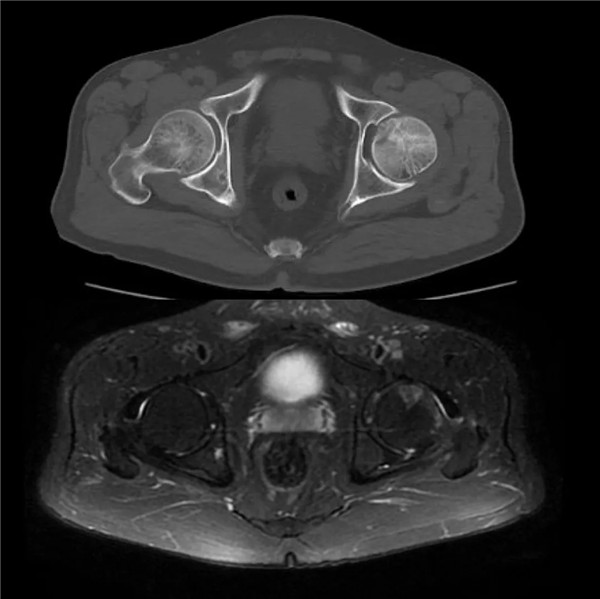

經(jīng)查體及拍片檢查后,副院長(zhǎng)危立軍診斷為“髖關(guān)節(jié)撞擊綜合征合并股骨頭壞死”,建議其入院,并接受手術(shù)治療。

當(dāng)天上午,余大伯入住我院關(guān)節(jié)科病區(qū)。廣安骨科中心副主任、關(guān)節(jié)科主任羅軍在查體時(shí)進(jìn)一步確診為股骨髖臼撞擊綜合征、股骨頭壞死早期,建議開展關(guān)節(jié)鏡微創(chuàng)手術(shù)治療。在與家人商量后,余大伯決定手術(shù)。

(CT和磁共振顯示:髖關(guān)節(jié)撞擊征合并股骨頭壞死)